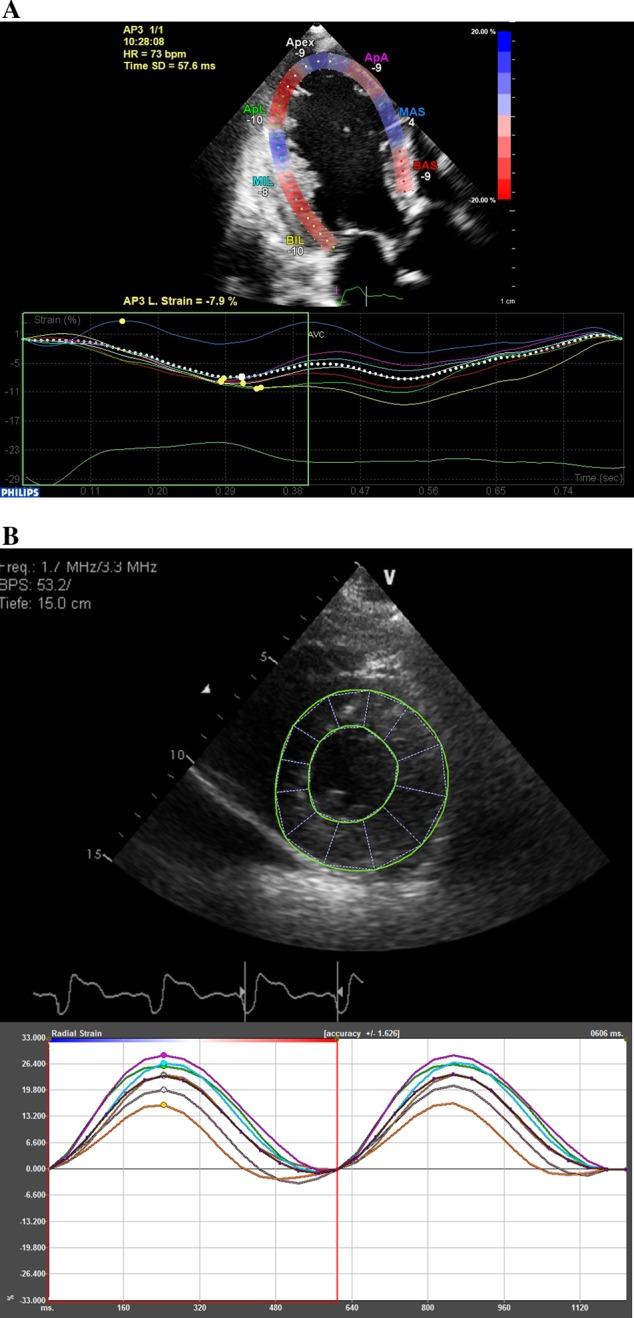

Cardiac resynchronisation therapy (CRT) can profoundly improve outcome in selected patients with heart failure; however, response is difficult to predict and can be absent in up to one in three patients. There has been a substantial amount of interest in the echocardiographic assessment of left ventricular dyssynchrony, with the ultimate aim of reliably identifying patients who will respond to CRT. The measurement of myocardial deformation (strain) has conventionally been assessed using tissue Doppler imaging (TDI), which is limited by its angle dependence and ability to measure in a single plane. Two-dimensional speckle-tracking echocardiography is a technique that provides measurements of strain in three planes, by tracking patterns of ultrasound interference ('speckles') in the myocardial wall throughout the cardiac cycle. Since its initial use over 15 years ago, it has emerged as a tool that provides more robust, reproducible and sensitive markers of dyssynchrony than TDI. This article reviews the use of two-dimensional and three-dimensional speckle-tracking echocardiography in the assessment of dyssynchrony, including the identification of echocardiographic parameters that may hold predictive potential for the response to CRT. It also reviews the application of these techniques in guiding optimal LV lead placement pre-implant, with promising results in clinical improvement post-CRT.

心脏再同步化治疗(CRT)可显著改善部分心力衰竭患者的预后;然而,反应难以预测,高达三分之一的患者可能无反应。人们对超声心动图评估左心室不同步性有着浓厚兴趣,最终目的是可靠地识别出对CRT有反应的患者。心肌变形(应变)的测量传统上使用组织多普勒成像(TDI)进行评估,其受角度依赖性和单平面测量能力的限制。二维斑点追踪超声心动图是一种通过在整个心动周期中追踪心肌壁内超声干涉模式(“斑点”)来提供三个平面应变测量的技术。自15年前首次使用以来,它已成为一种比TDI能提供更可靠、可重复且敏感的不同步性标志物的工具。本文综述了二维和三维斑点追踪超声心动图在评估不同步性中的应用,包括识别可能对CRT反应具有预测潜力的超声心动图参数。还综述了这些技术在指导植入前最佳左心室电极放置中的应用,在CRT后临床改善方面取得了有前景的结果。